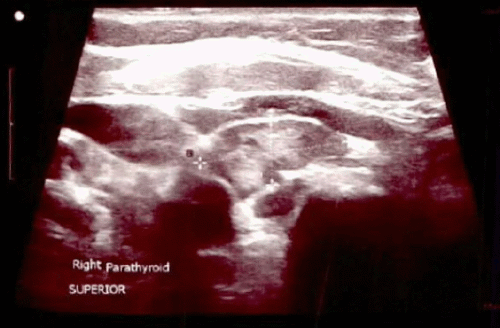

The patient was diagnosed with tertiary hyperparathyroidism due to longstanding secondary hyperparathyroidism. Given her low bone mass and increased bone resorption, alendronate was initiated and slowly titrated up to avoid potential hypocalcemia. Cinacalcet was also prescribed but was never initiated due to cost. After a year of medical therapy, her PTH had worsened (1976 pg/mL), and urine NTx (246 nmol/mmol creatinine) was still elevated. At that point, she was referred to endocrine surgery for her tertiary hyperparathyroidism. Preoperative single-photon emission computed tomography combined with contrast-enhanced CT (SPECT/CECT) imaging demonstrated an enlarged parathyroid inferior to the right thyroid lobe measuring approximately 1.7 × 1.4 × 2.7 cm with focal sestamibi uptake (Figure 1). Surgical clinic ultrasound confirmed the presence of a hypoechoic structure in the corresponding location, which appeared to potentially be two abutting right-sided parathyroid glands (Figure 2). Our clinical practice is to routinely perform preoperative SPECT hybridization with contrast-enhanced CT scanning (SPECT/CECT) to aid in identifying and localizing any ectopic parathyroid glands. We additionally routinely perform an in-office ultrasound to aid in preoperative parathyroid gland localization and rule out concomitant thyroid pathology before taking a patient to the operating room.

Figure 2. Surgical Clinic Ultrasound Findings. A) Right Superior Parathyroid and B) Right Inferior Parathyroid. Published with Permission

A.

B.